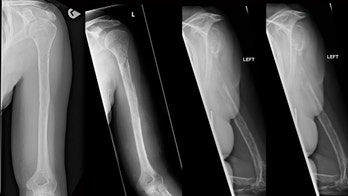

Orthopedics - Page 49